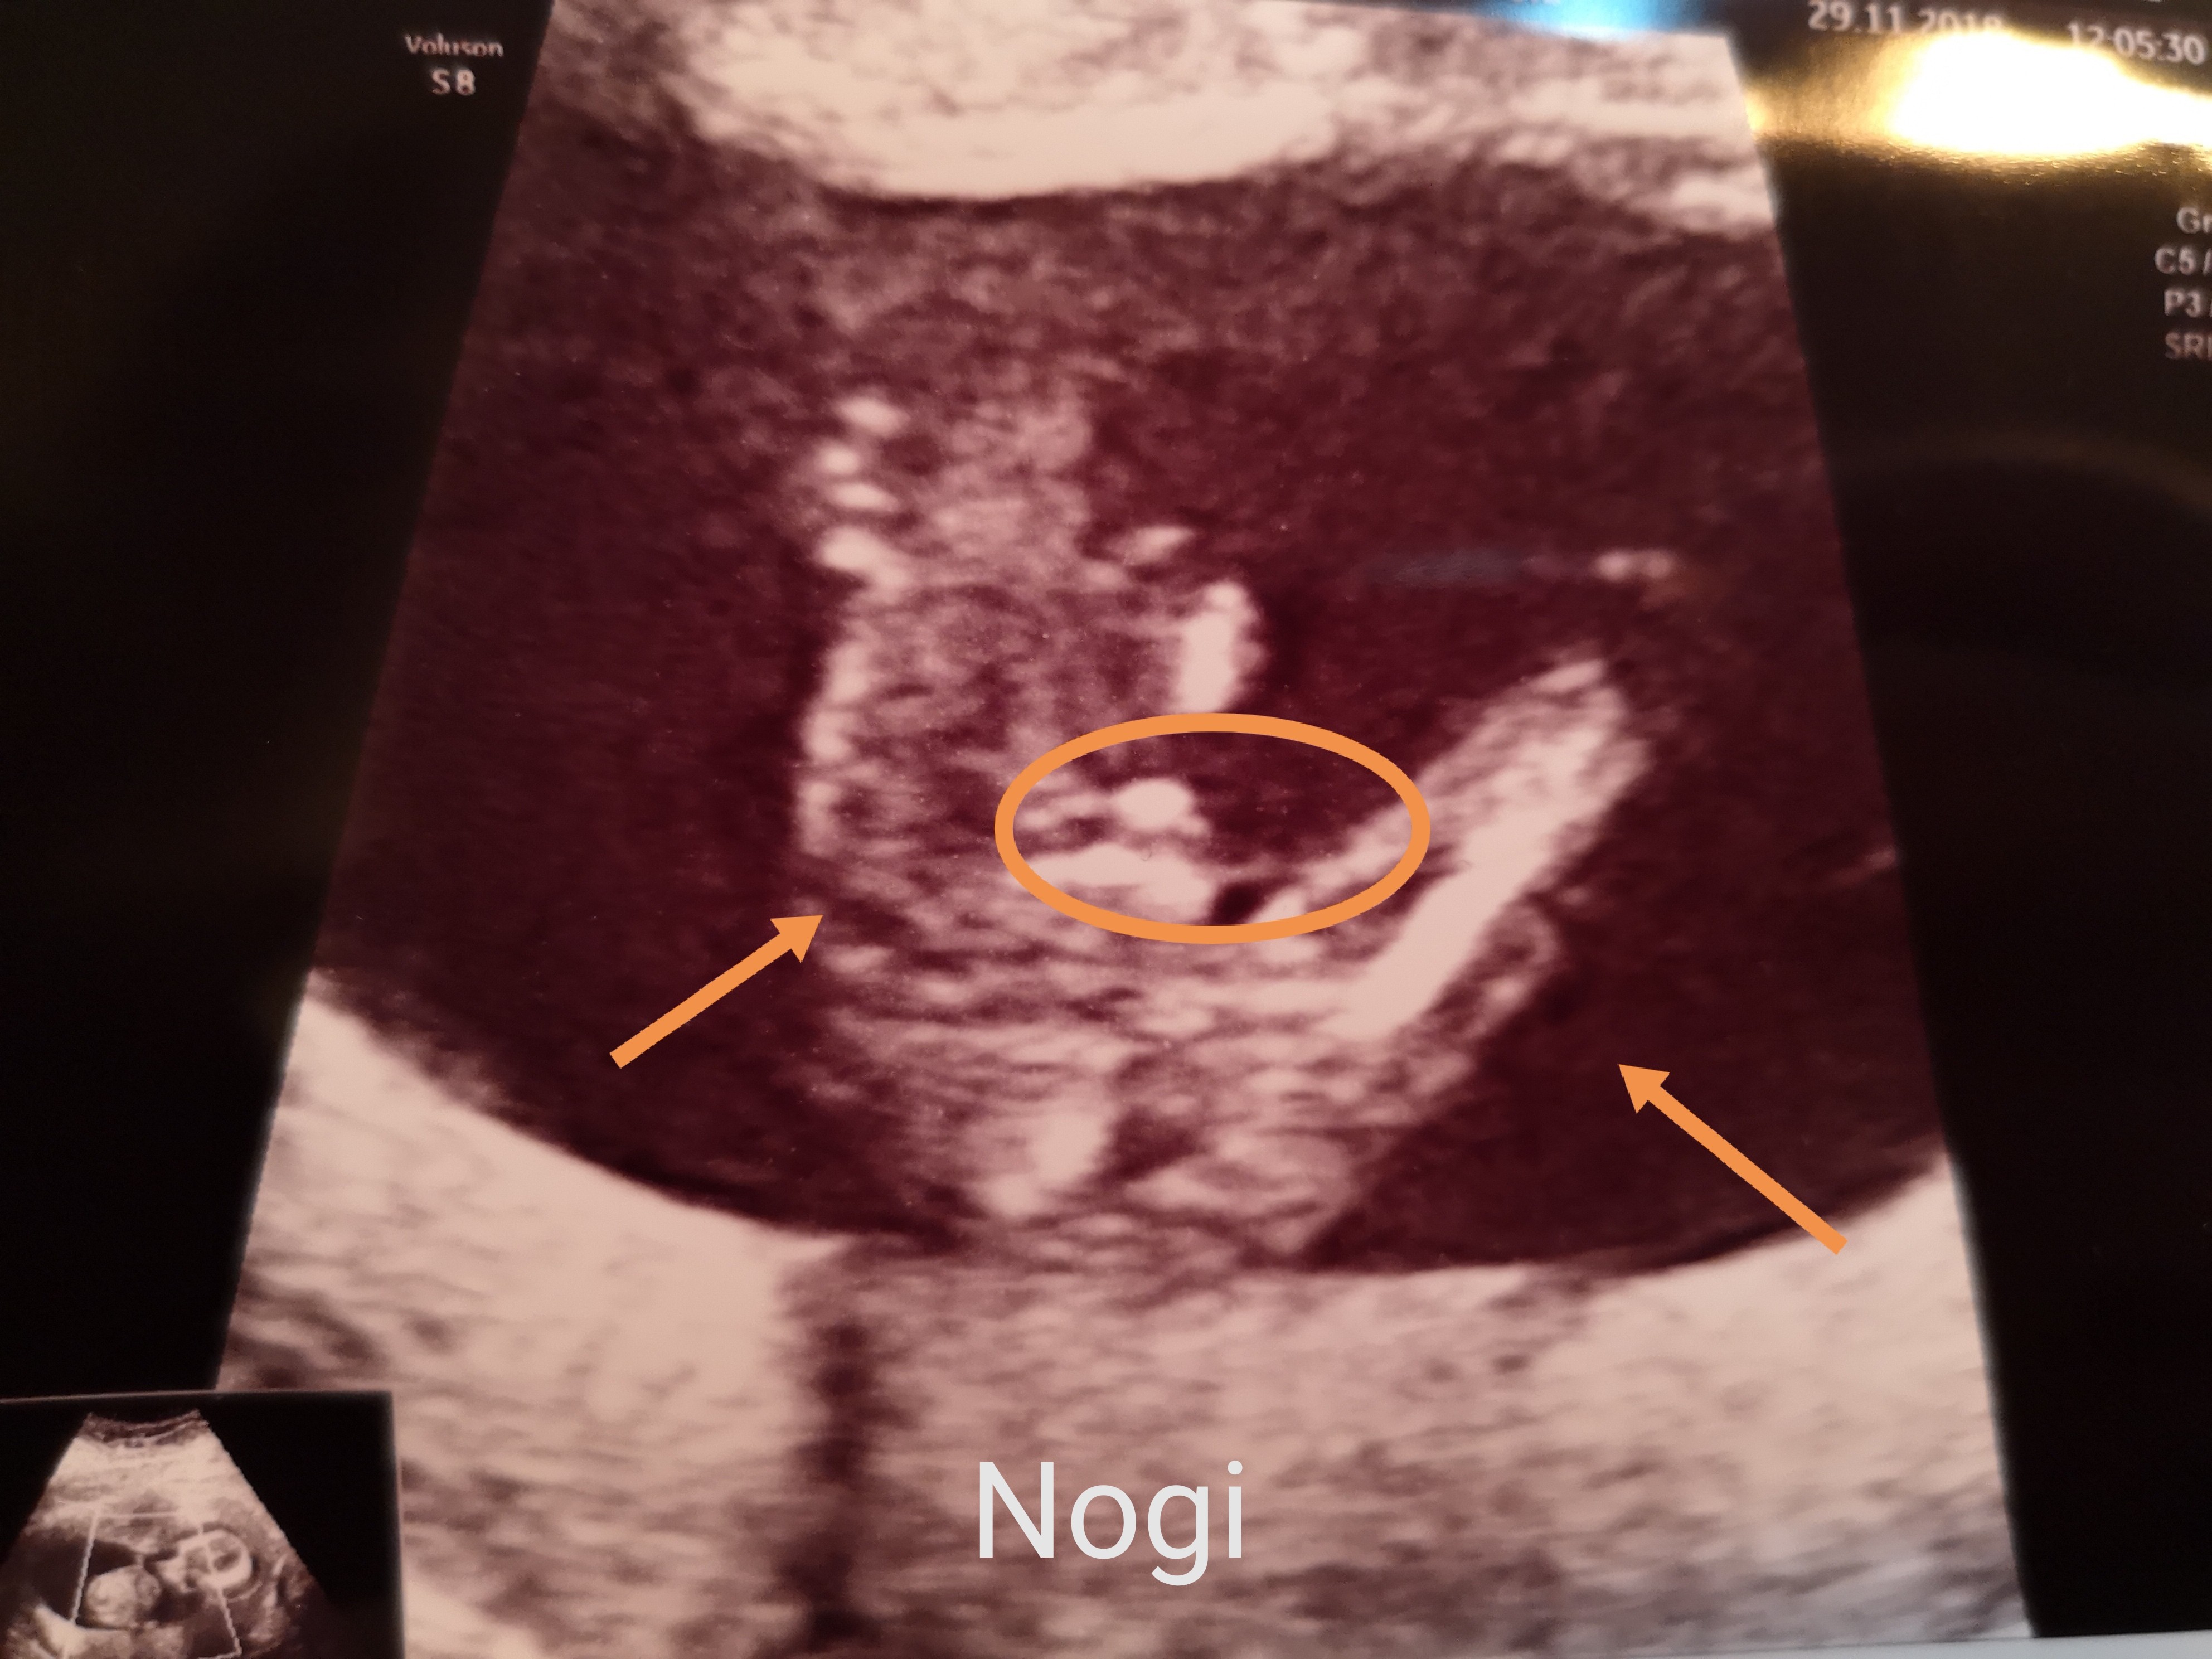

Witam w 19 tygodniu ciąży dowiedziałam się ze będę miała dziewczynkę w 20 tyg okazało się jednak , że to chłopak. Sama już nie wiem bo na jednym usg widać na pewno dziewuche a na drugim chłopca. Może to pempowina ?? Może ktoś mi pomoże rozwiązać ta zagadkę